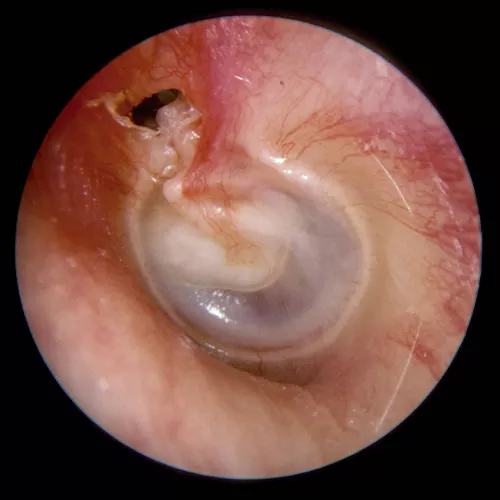

La otoscopia es la prueba fundamental para el diagnóstico, siendo definitiva en una parte importante de los casos. Existen muchas anomalías en la membrana timpánica asociadas a la otitis serosa. Por lo general, muestra un tímpano íntegro, edematizado y opaco con un aumento de la vascularización radial, y puede estar en posición normal, abombado o retraído. En los procesos de corta evolución la coloración suele ser rojiza, generalmente con una membrana engrosada. Sin embargo en los casos crónicos el aspecto suele ser azulado, resultado del depósito de hemosiderina en el exudado, y la membrana suele estar adelgazada y atrófica, con tendencia a la retracción, pudiendo desencadenar en una otitis adhesiva. En los casos en que el tímpano conserva su transparencia, es posible observar en ocasiones niveles o burbujas (indicativo de que la trompa funciona parcialmente).